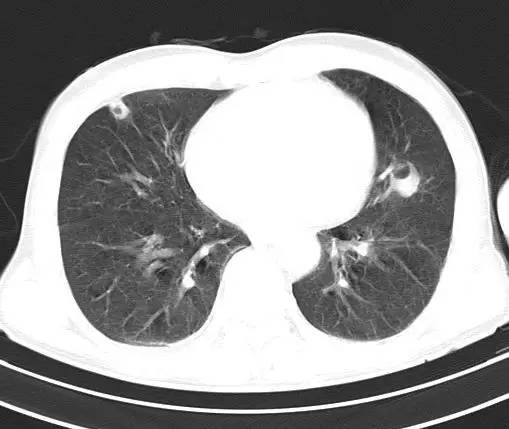

治疗后十天CT(图9-12):双肺病灶明显缩小,有所吸收。

金黄色葡萄球菌肺炎,抗炎治疗23天后完全吸收。